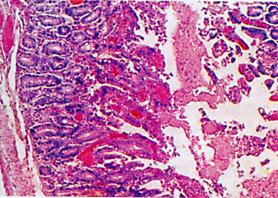

小腸是所有營(yíng)養(yǎng)物質(zhì)消化和吸收的主要場(chǎng)所。一直以來(lái),人們都很少關(guān)注小腸自身的營(yíng)養(yǎng),而隨著人們對(duì)小腸營(yíng)養(yǎng)的認(rèn)識(shí),發(fā)現(xiàn)小腸自身的營(yíng)養(yǎng)對(duì)其功能的發(fā)揮具有重要意義。